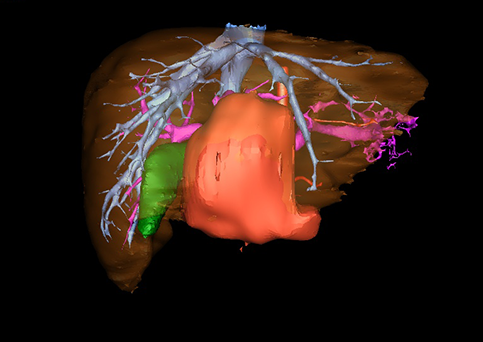

近年来由于数字医学的发展,基于可视化三维重建技术的计算机辅助手术系统极大推进了小儿肝脏肿瘤的精准手术的进步。可以立体透视肝脏解剖、精确掌握肝段的边界、精确测算肝段乃至任意血管所支配的功能体积、准确定位病灶及其与邻近血管的解剖关系,最终对不同手术方案进行比较、筛选和优化。因此,计算机辅助手术规划系统是实现精准肝切除的有力辅助工具,是未来数字外科、精准外科等21世纪外科新理念的重要技术支撑。

计算机辅助手术规划系统具有良好的操作可行性、计算准确性和三维显示效果,可半透明、交互式显示真实的肝内立体解剖关系和空间管道变异,准确计算肝内管道的直径、走行角度,两点间的垂直距离,和任意血管的支配或引流范围等传统二维影像无法获取的信息,有助于实施个体化手术,提高了手术的确定性、预见性和可控性。计算机辅助手术规划系统可直观显示预留肝脏的结构和功能,并可通过虚拟切割功能辅助术者对手术方案进行蹄选和优化,系统评估手术风险和制定对策,改变了部分二维规划的术式和切除范围,使部分二维规划认为不能切除的患者成功手术,提高了手术的根治性、安全性和病变的可切除性,更加符合精准肝脏外科的术前规划要求。详见第11章。

随着计算机技术及影像检查技术的不断发展,以精确的术前影像学和功能评估、精细的手术操作为核心的精准肝切除技术日益受到重视。基于数字医学的计算机辅助手术技术(computer-assisted surgery,CAS)则是实现肝脏精准手术操作的基础。计算机辅助手术系统(CAS)可将术前二维(two dimensional,2D)的CT/MRI影像数据进行三维(three dimensional,3D)重建,建立个体化的肝脏三维解剖模型,清晰显示肝脏内脉管系统的走行及解剖关系,还原病灶与其周围脉管结构的立体解剖构象,准确地对病变进行定位、定性和评估,制定合理、定量的手术方案,实施个体化的肝脏血管取舍分配方案及实施精准肝脏手术。一般认为CAS包括:创建虚拟的患者的图像;患者图像的分析与深度处理;诊断、手术前规划、手术步骤的模拟;术中实时导航。应用本技术后,由于可以更清晰地看出肿瘤的界限,特别是根据肝血管的显影,判断出肿瘤与门静脉及肝静脉的关系以在手术前较准确地估计出手术成功切除的可行性。以往部分根据普通强化CT判断无法手术的病例而被评估为可以成功切除并手术成功。